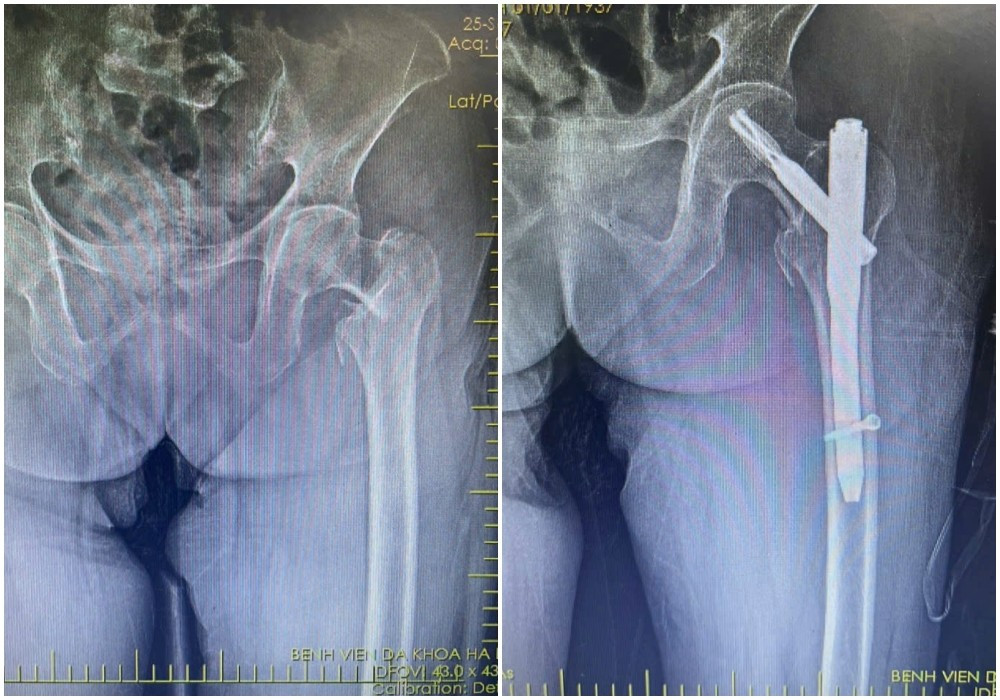

Hình ảnh X-quang gãy liên mấu chuyển xương đùi trái của bệnh nhân H (88 tuổi) được kíp mổ phẫu thuật kết hợp xương ít xâm lấn - Ảnh BVCC

Kết quả chụp X-quang xác định bệnh nhân bị gãy liên mấu chuyển xương đùi. Với tình trạng tuổi cao, sức yếu, việc vận chuyển bệnh nhân hạn chế, tiềm ẩn nguy cơ làm vị trí gãy thêm trầm trọng.

Qua đường rạch da nhỏ khoảng 3-5cm, phẫu thuật viên nắn chỉnh xương gãy về vị trí giải phẫu, sau đó cố định bằng đinh nội tủy PFNA dưới màn hình tăng sáng (C-arm).